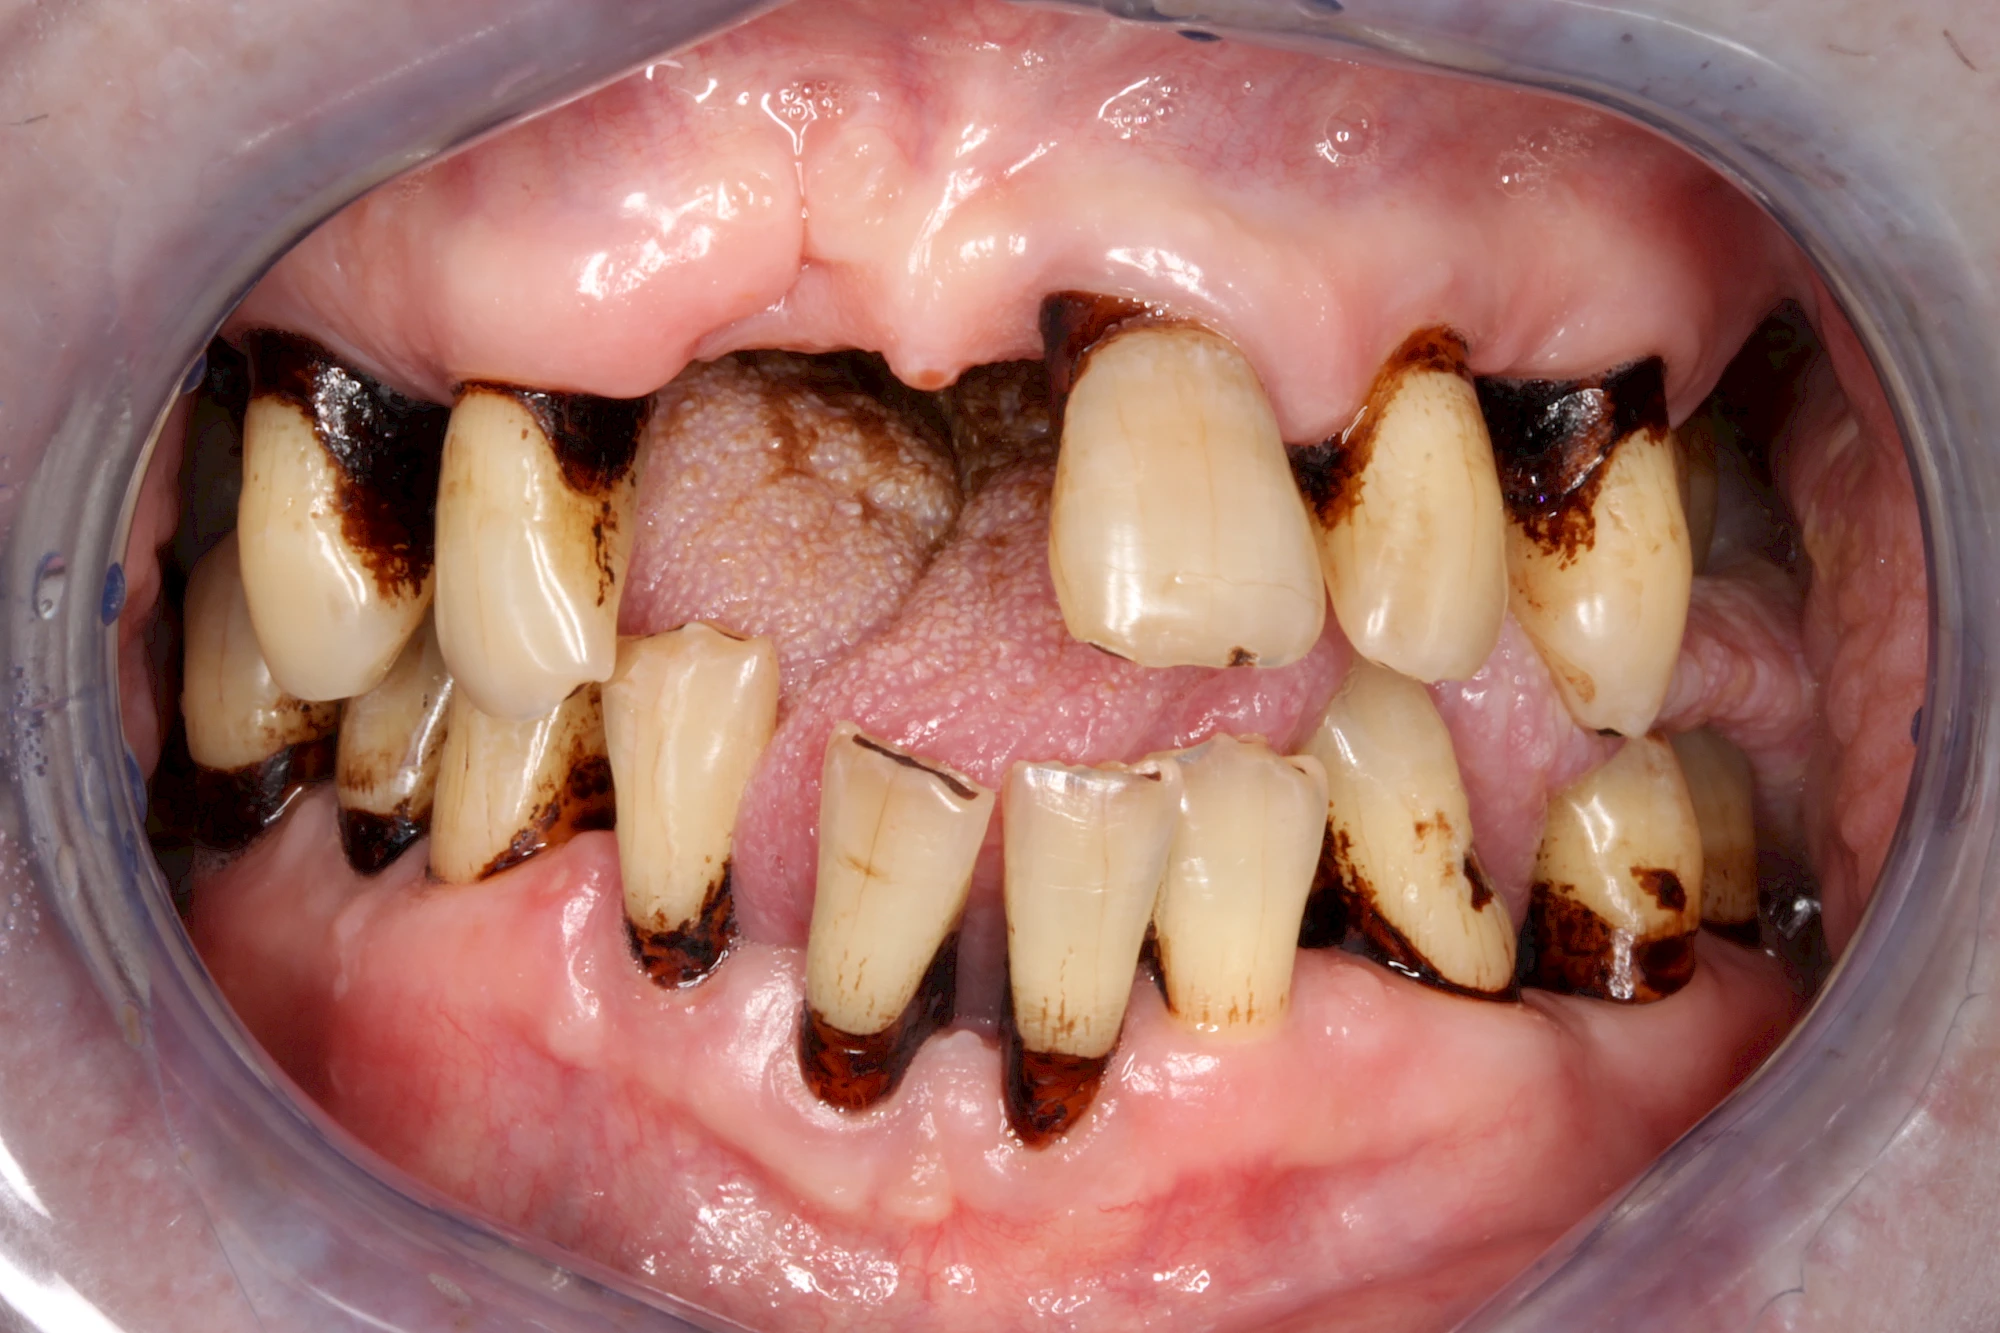

Dunkle bzw. Rötliche Verfärbung

Ist ein einzelner Zahn deutlich dunkler als die Nachbarzähne kann das ein Zeichen sein, dass der Nerv abgestorben ist. Unter Umständen wurde bereits eine Wurzelkanalbehandlung vom Zahnarzt durchgeführt. Eine Abklärung durch den Zahnarzt ist in jedem Fall sinnvoll.